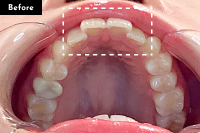

Basicプラン

上下前歯12本の部分矯正

20代 女性

治療費用:Basic 33万円(税込)

治療期間:4ヶ月

- Before

After